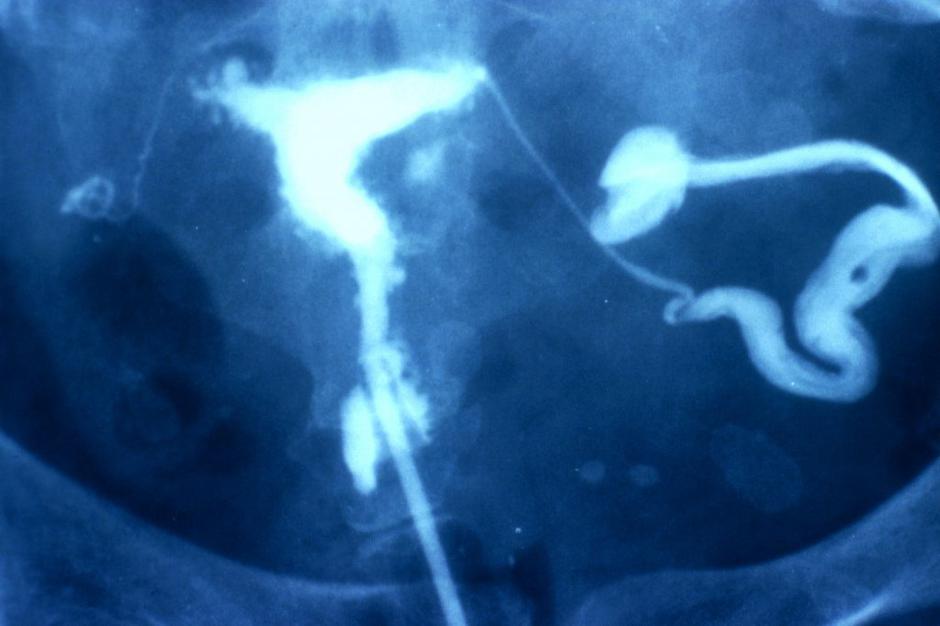

Endometrioza je stanje, pri katerem se tkivo, podobno sluznici maternice, pojavi ali razvije zunaj maternice, kar poleg bolečin povzroča tudi neplodnost.

Endometrioza | Avtor: Profimedias Profimedias